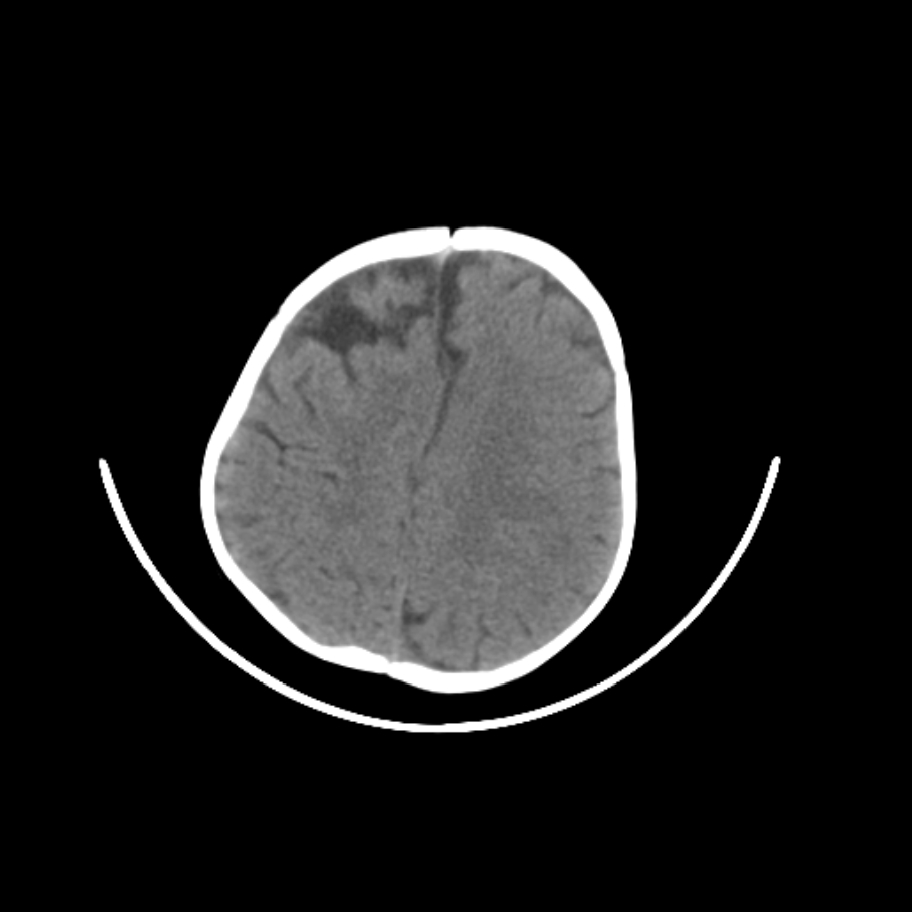

以下是引用随光逐影在2009-4-8 7:51:00的发言:[br]1)透明隔缺如(视-隔发育不良?)。2)右侧脑裂畸形。3)右侧幕上半球脑萎缩。